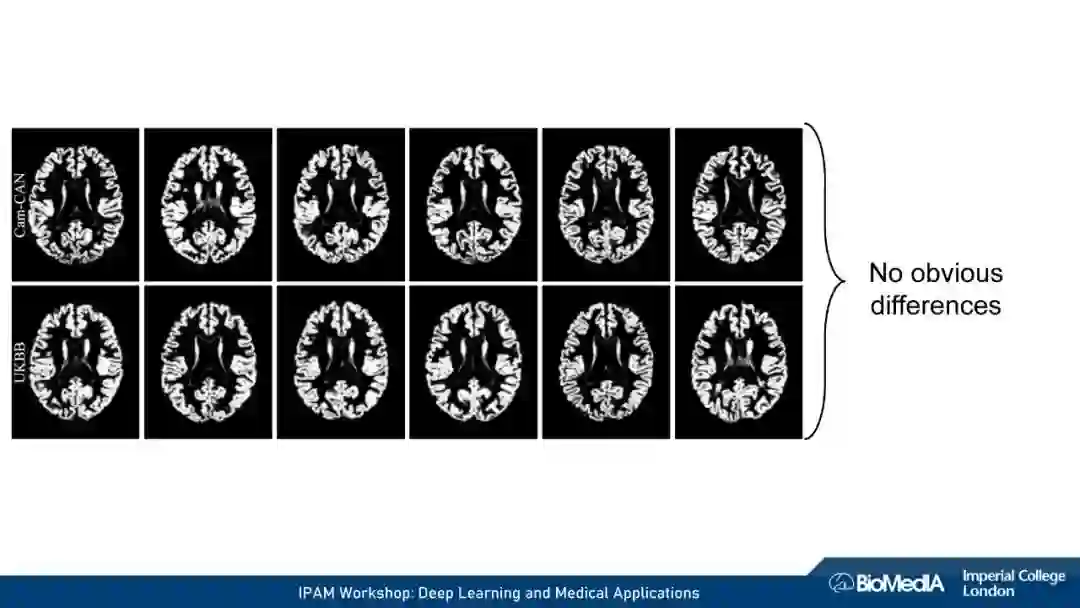

我们使用因果推理来阐明医学成像的关键挑战:1) 数据稀缺,即高质量注释的有限可用性 2) 数据不匹配,即训练有素的算法可能无法在临床实践中推广。我们认为,图像、注释和数据收集过程之间的因果关系不仅会对预测模型的性能产生深远的影响,甚至可能决定首先应该考虑哪种学习策略。例如,半监督可能不适合于图像分割——这可能是我们在医学图像分析中因果关系考虑的一个令人惊讶的见解。我们的结论是,对于基于机器学习的图像分析的成功至关重要的是,研究人员要能意识到并解释他们的数据背后的因果关系。